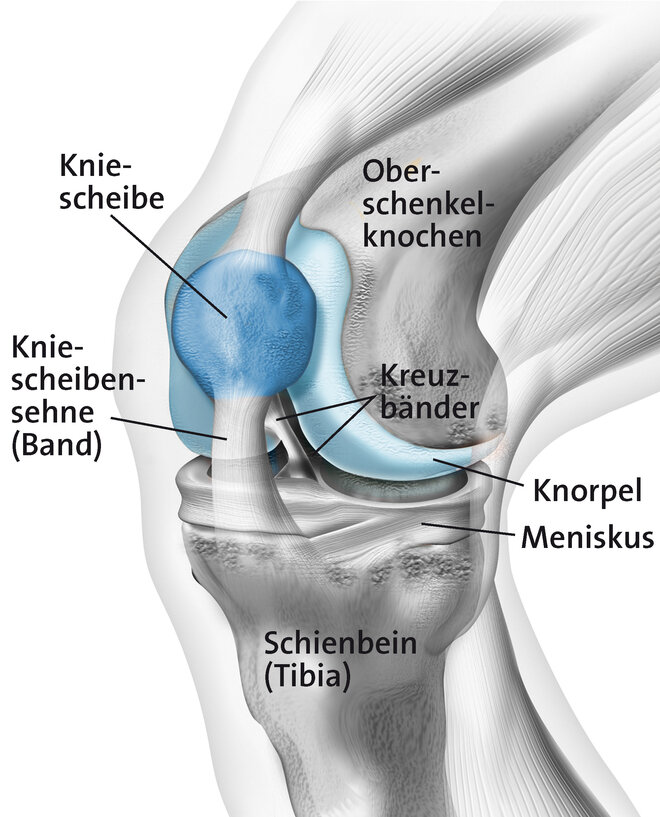

Durch Überbelastung der Kniescheibensehne (Patellarsehne) kommt es an ihrem Ursprung am Unterrand der Kniescheibe zu kleinsten Verletzungen und Auffaserungen der Sehne. In der Nähe bildet sich neues Bindegewebe, Nerven und Blutgefäße sprießen ein. Ärzte sprechen auch von degenerativen Veränderungen. Der allgemeine Fachbegriff ist Tendinopathie (= Sehnenleiden). Zu einer Überlastung der Patellarsehne kommt es vor allem durch sportliche Aktivität, insbesondere bei sogenannten Schnellkraft-Sportarten mit raschen Richtungswechseln, abruptem Abbremsen ("stop and go") und starker Belastung beim Springen und Landen wie beispielsweise Volleyball oder Handball. Daher auch der Begriff Springerknie (englisch: jumpers knee). Betroffen können ein oder beide Knie sein. Meist ist die Sehne am unteren Pol der Kniescheibe betroffen (Insertionstendinose).

Tendinopathien, also Schmerzen an den Sehnen können an verschiedenen Stellen auftreten. Beim Jumpers-Knee handelt es sich um eine Entzündung am Ansatz der Sehne (Insertionstendinose) am unteren Pol der Kniescheibe. Diese tritt vor allem beim sportlichen Erwachsenen auf. Treten die Beschwerden bereits beim Jugendlichen auf handelt es sich meist um einen Morbus Sinding-Larson-Johansen. Auch hierbei kommt es durch Überbelastung zu einer Entzündung am Ursprung der Patellarsehne, bei welcher aber ein Teil der Kniescheibe mitabsterben kann (Osteonekrose).

Hintergrundinformation - Das Kniegelenk